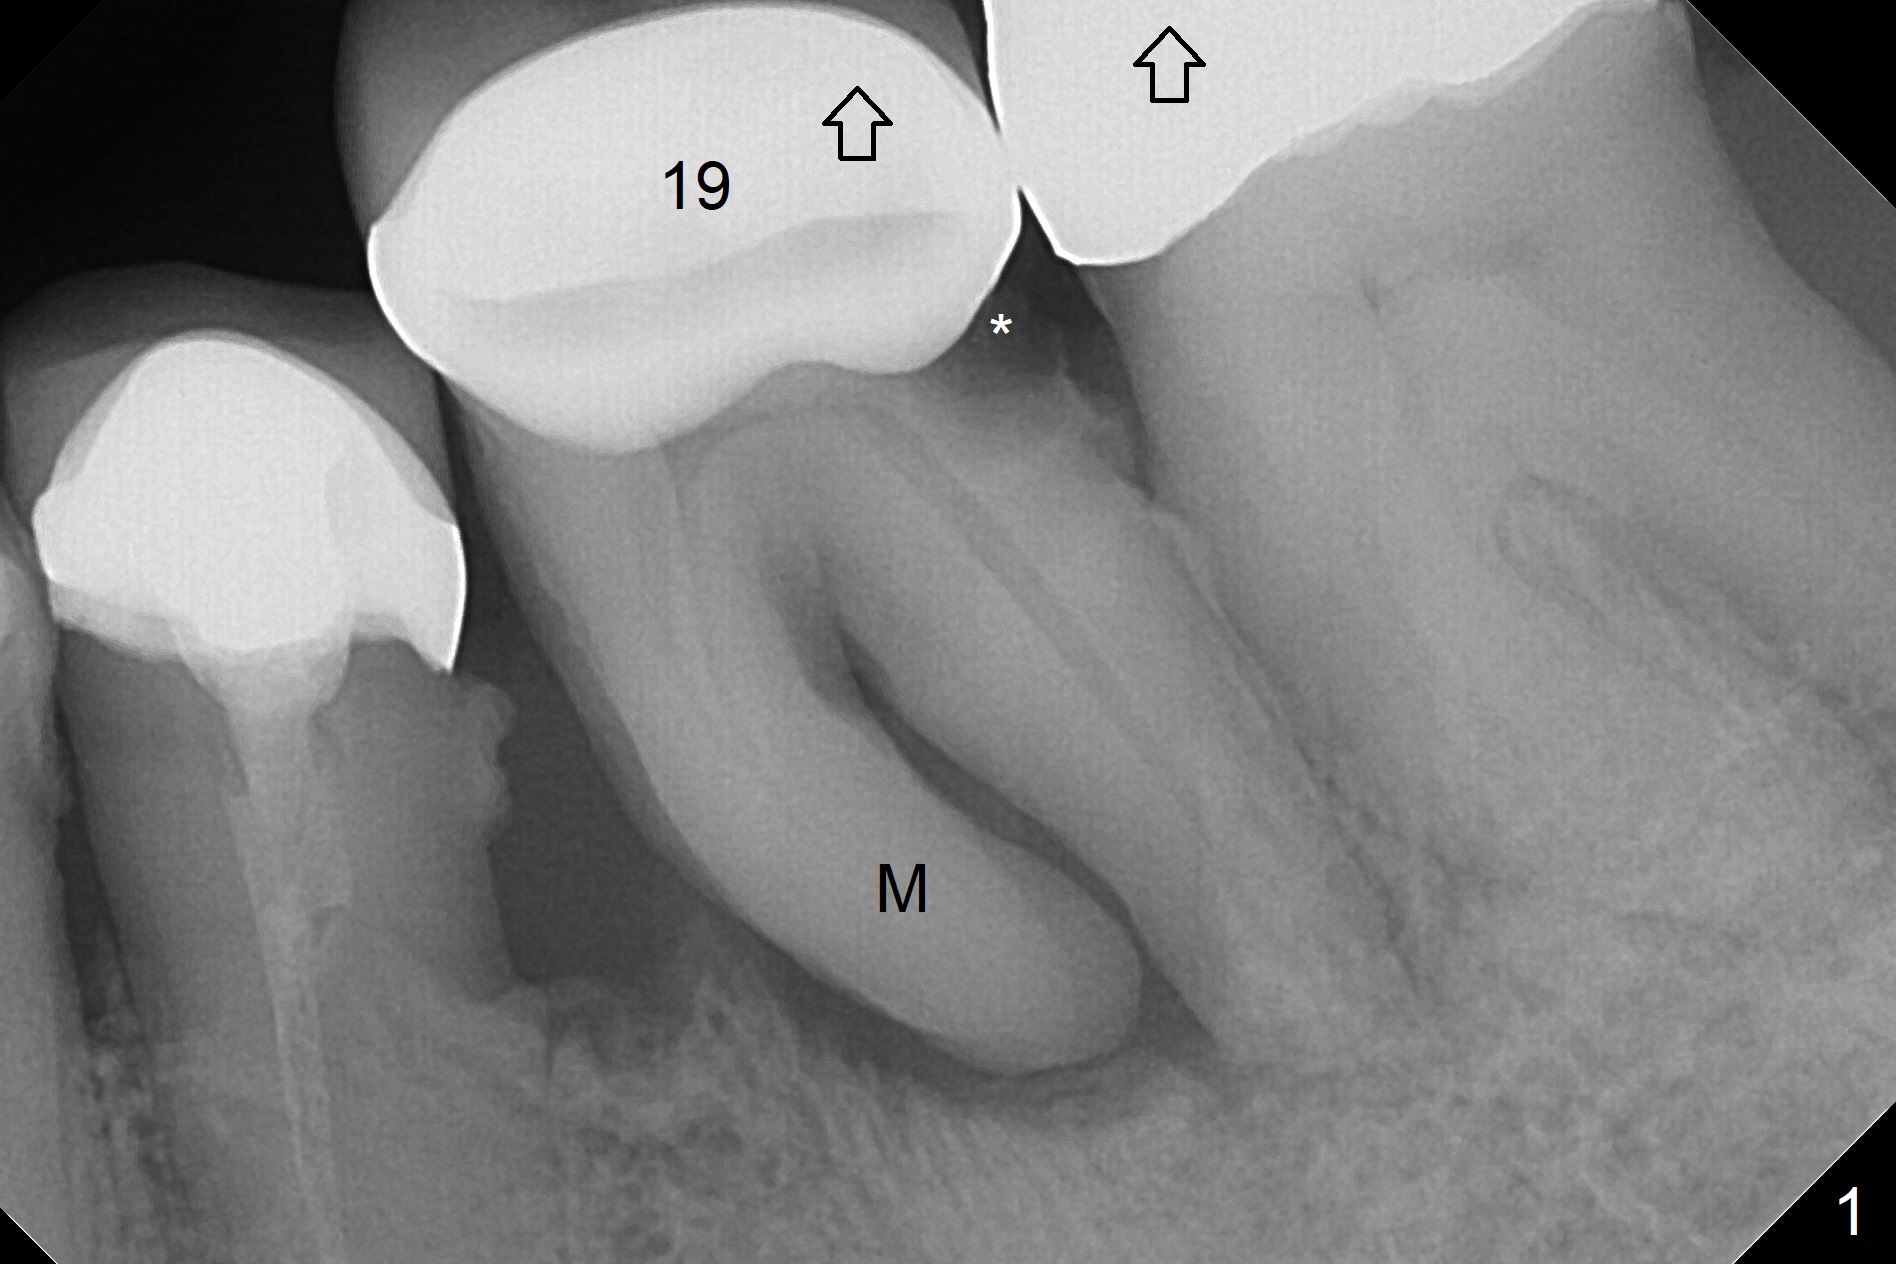

Supraerupted Molar Five months post cementation of #29-31 implant FPD of a 72-year-old man, the supraerupted (Fig.1 arrow) tooth #19 fails (caries (*) and mesial (M) root radiolucency). A 14 mm long implant (Fig.2 green) will be placed deep with 6 mm cuff (pink) and 4 mm abutment (blue). Return to Lower Molar Immediate Implant, Prevent Molar Periimplantitis (Protocols, Table), Armaments, Metronidazole Xin Wei, DDS, PhD, MS 1st edition 06/05/2018, last revision 06/12/2018 |